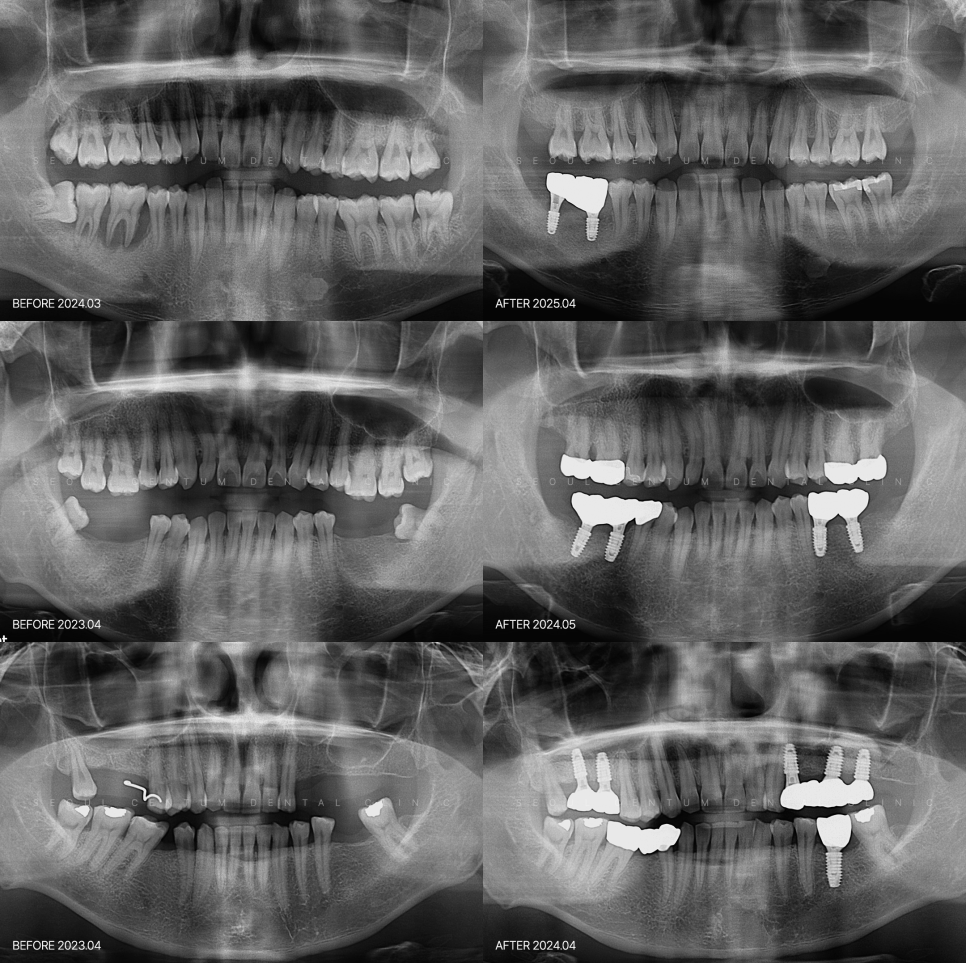

이 때문에 CT, 파노라마 엑스레이 등의 촬영으로

뼈의 두께와 높이, 신경과의 위치를

정확히 파악 후 진행합니다.